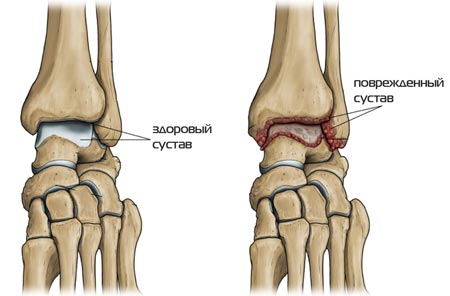

Деформация

Этот симптом появляется от того, что на поверхностях кости, хряща появляются наросты. Из-за постоянного раздражения активизируется выработка синовиальной жидкости, отчего орган отекает.

Важно! Деформация является одним из поздних симптомов артроза. Сустав уже поражен болезнью в значительной степени, и часто консервативное лечение не приносит результатов.